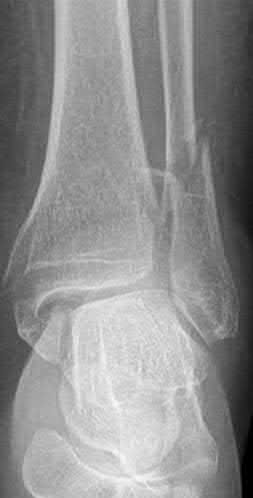

A 34-year-old male sustains the closed injury seen in Figure A as a result of a high-speed motor vehicle collision. What is the most appropriate next step in treatment?

The radiograph shows a comminuted pilon fracture, which is associated with high-energy trauma and significant soft tissue injury. The tested concept here is the importance of avoiding definitive reduction and fixation of this high-energy injury, which has been shown to be associated with an increased risk of wound complications and deep infections (as compared to staged treatment with usage of a spanning external fixator).

Patterson et al. reviewed 23 consecutive patients with comminuted distal tibia fractures. They showed 0% infections or wound-healing problems in their patient population treated with a two-staged protocol. Their protocol involved fibula fixation with an intramedullary implant and application of a medial external fixator to to regain length and restore anatomic alignment. Reevaluation of the limb occurred ten to fourteen days later for definitive fixation.

Sirkin et al. retrospectively reviewed 40 closed and 17 open pilon fractures (AO types 43A-C) that were treated with staged surgical management (avg. time from ext. fix. to formal reconstruction was 14 days (range 4 to 31) They reported 17% post-operative wound complication in the closed group and 11% post-operative wound complication in the open group (Gustilo Type I-III). They suggest the technique was successful in both closed and open pilon fractures.